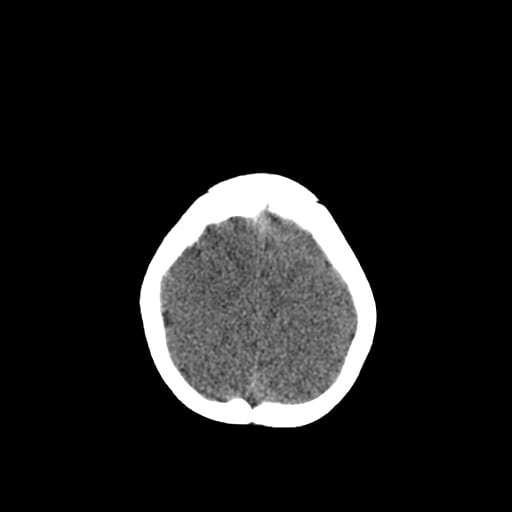

Age: 1

Sex: Male

Indication: Fall